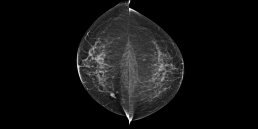

73-year-old woman, screening.

Mammoscreen points to a suspicious lesion (red flag) in both the right and left breast but also a possible deep suspicious lesion of the left breast.

A biopsy is performed on the suspicious lesions of the right breast and the left breast; the biopsy finds an infiltrating ductal carcinoma in the right breast and a lobular component carcinoma in the left.

A breast MRI confirms the suspicious character of the deep rounded lesion of the left breast classified orange (MammoScreen Score™ of 6).

A marking by harpoon is placed on the 3 lesions; the surgery confirms that the deep nodular image on the left corresponds to an infiltrating ductal carcinoma.